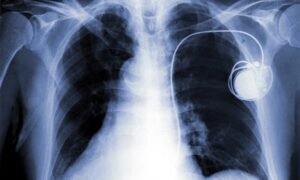

Togo : L’hôpital de Notsè dévoile sa dernière arme pour lutter contre les maladies cardiaques Lire la suite »